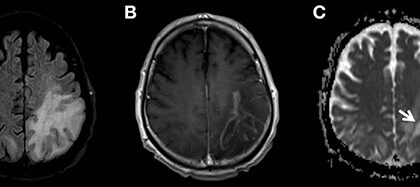

Global Progressive Multifocal Leukoencephalopathy Treatment Industry Aims for US$ 1,773.97 Million by 2033, Redefining Neurological Treatment Landscape

The Global Progressive Multifocal Leukoencephalopathy (PML) Treatment Industry is on the brink of a transformative